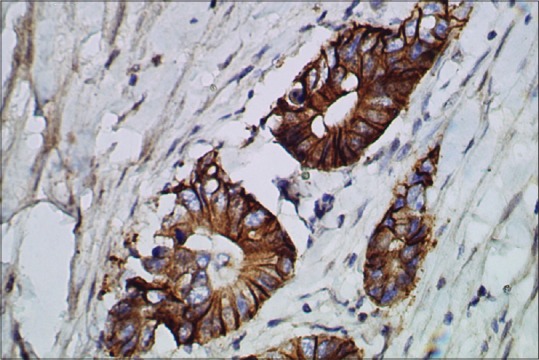

Immunohistochemistry for HER2/neu showed a score of 3+ positivity [Figure 3] in 8 cases (17.1%), all were adenocarcinoma of intestinal variant having well and moderate differentiation [Tables [Tables22 and and3]3] and originated from the body and pyloroantrum (four each). HER2 score was 2+ [Figure 4] in 7 cases (14.9%) these were again well to moderately differentiated adenocarcinoma of the intestinal variant. HER2 score was 1+ or 0 [Figure 5] in 32 cases (68.1%). In this group, 13 cases (40.6%) were graded as poorly differentiated, and among them eight cases were diffuse variant of adenocarcinoma. Only two cases of poorly differentiated, one of moderately differentiated carcinoma of intestinal variant and four cases of well-differentiated carcinoma showed 2+ HER2 positivity. Well and moderately differentiated carcinoma showed more HER2 3+ positivity (8 cases, 25%), whereas cases of poorly differentiated carcinoma predominantly (86.7%) showed the lack of HER2 expression. HER2 positivity score of 2+ was noted in seven cases of Stage III disease, whereas score 3+ was noted four cases each of Stage III and Stage IV disease, respectively. HER2 score was analyzed according to the grade of adenocarcinoma [Table 4]. A score of 2+ or 3+ was noted in 13 (40.6%) cases of well and moderately differentiated carcinoma but none in poorly differentiated carcinoma.

| Figure 3:Well-differentiated adenocarcinoma showing human epidermal growth factor receptor 2 score of 3+ (human epidermal growth factor receptor 2 immunostain, ×400)